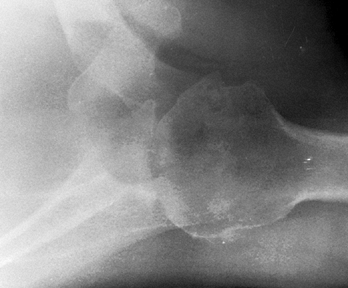

from the severe, unpredictable destruction of both bone and soft

tissue, which is the hallmark of the disease (Fig. 101.51, Fig. 101.52, Fig. 101.53 and Fig. 101.54). Severe medial and superior wear of the

Figure 101.51.

Rheumatoid arthritis of the shoulder. Superior migration of the humeral head, cyst formation, marginal erosion, and severe joint destruction. |